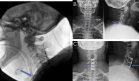

A nivel musculoesquelético, presentaba sinovitis bilateral, desviación cubital de ambas manos y deformidades en las articulaciones metacarpofalángicas (MCF) e interfalángicas proximales (IFP), además de compromiso en las metatarsofalángicas (MTF).

Las radiografías de manos y pies revelaron erosiones óseas periarticulares y estrechamiento del espacio articular, sin signos evidentes de osteopenia típica de la artritis reumatoide clásica.